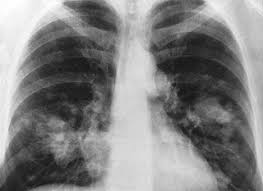

Les fibres d’amiante, extrêmement fines et volatiles, se dispersent facilement

dans l’air (usure, travaux…). Une personne exposée à l’amiante

peut développer un certain nombre de troubles de la santé, dont

des cancers, principalement pulmonaires. Détecter la présence

d’amiante

à travers les contrôles effectués est donc essentiel à plus

d’un titre avant toute transaction immobilière.